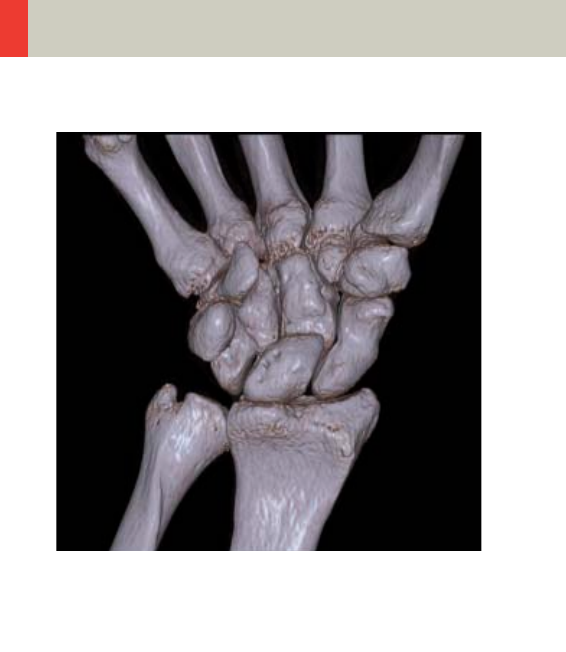

- Upper Extremities